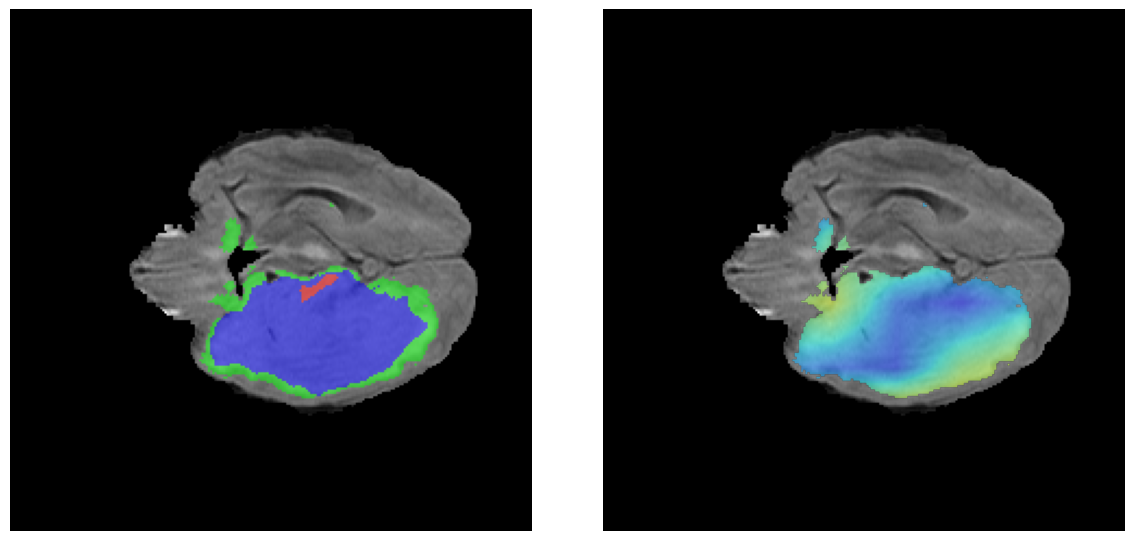

Ejemplos LGG - Atención Difusa en Edema Peritumoral

LGG Grad-CAM++ 1 LGG Grad-CAM++ 2 LGG Grad-CAM++ 3 LGG Grad-CAM++ 4 LGG Grad-CAM++ 5 LGG Grad-CAM++ 6

Para casos LGG, la atención del modelo es más difusa y se concentra principalmente en la región de Edema Peritumoral (verde), consistente con la naturaleza más infiltrativa y menos agresiva de estos tumores.

El análisis Grad-CAM++ reveló que el modelo desarrolla automáticamente la capacidad de localizar las regiones tumorales. Para casos HGG, la atención se alinea fuertemente con las regiones de Tumor Realzado (ET) y Núcleo Necrótico (NCR). En contraste, los casos LGG muestran atención más difusa, principalmente concentrada en la región de Edema Peritumoral (ED), lo cual es consistente con la patofisiología conocida de los gliomas.